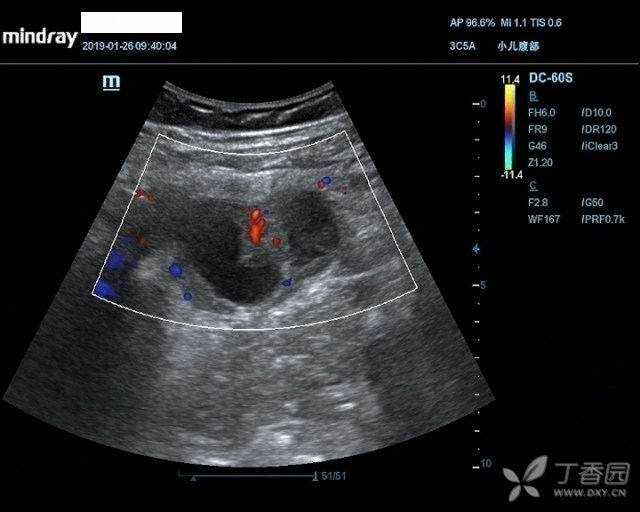

右心房内欧式瓣回声 - 超声医学讨论版 -丁香园论坛

图片尺寸1080x1920